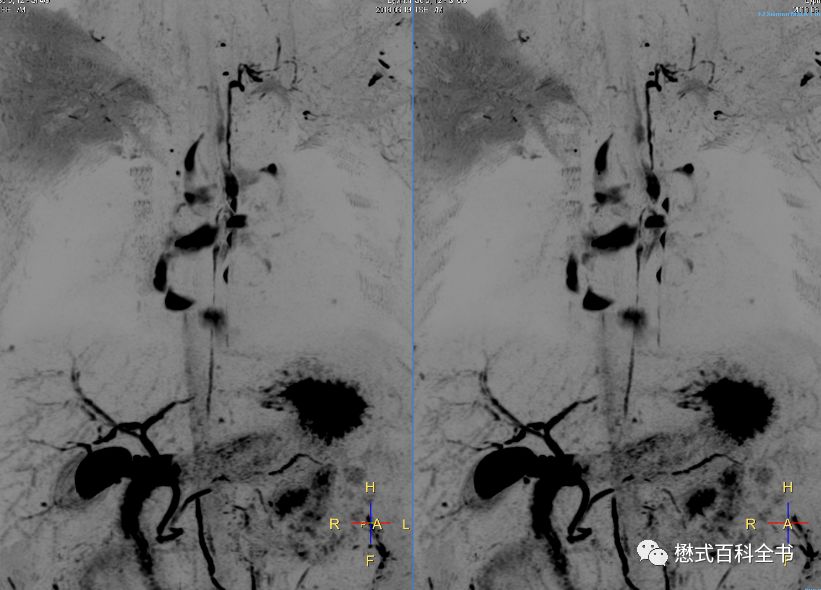

图2、3:ERCP图像

和MRCP类似的一个单词叫做ERCP(Endoscopic Retrograde CholangioPancreatography),翻译过来就是(经内镜)逆行性胰胆管造影术。Endo-是内、在内的前缀,-scopic表示观测、观察,当然endoscopic这个词本来就是内窥镜的,用内镜的方式的意思。Retro-是一个使用比较多的前缀,代表向后的,回顾的,*退倒**的。大家还记得我们的回顾性心电门控是怎么表述的吗?Retrospective,回顾性研究,回顾性分析都是这个前缀。grade这个单词大家熟悉,可以理解为年级、级别、阶段。

retrograde就很好理解了,为了信达雅和结合技术把它翻译为逆行性的。而同样的单词cholangiopancreatography在MRCP中翻译为成像,在ERCP中翻译为造影术更恰当。因为ERCP是一种有创性的手术方式,并且会注入造影剂以使胆囊及胆管系统显影,所以用造影术是比较合适的。